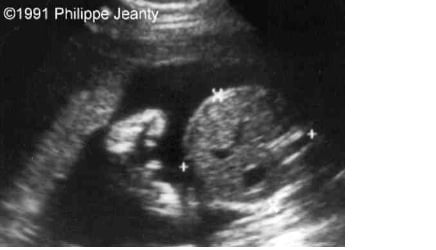

I got my 20 week US done yesterday ( this is my first baby!) and the tech told me we were having a boy. She didn't seem very confident though, and after comparing my friends' u/s of their baby boys I feel my baby may be a girl with either her umbilical cord showing or maybe she has some swelling?

• Totally looks like a boy. You can see the testicles and everything

• That looks all boy to me. Even without the "cord/penis" the bottom bits still do not look like a "hamburger on bun". :D

• That's a boy. My girl is very obviously a girl (3 white lines). You have a huge bulge in the absence of white lines. If it makes you feel better, name him Sue but he's still a boy.